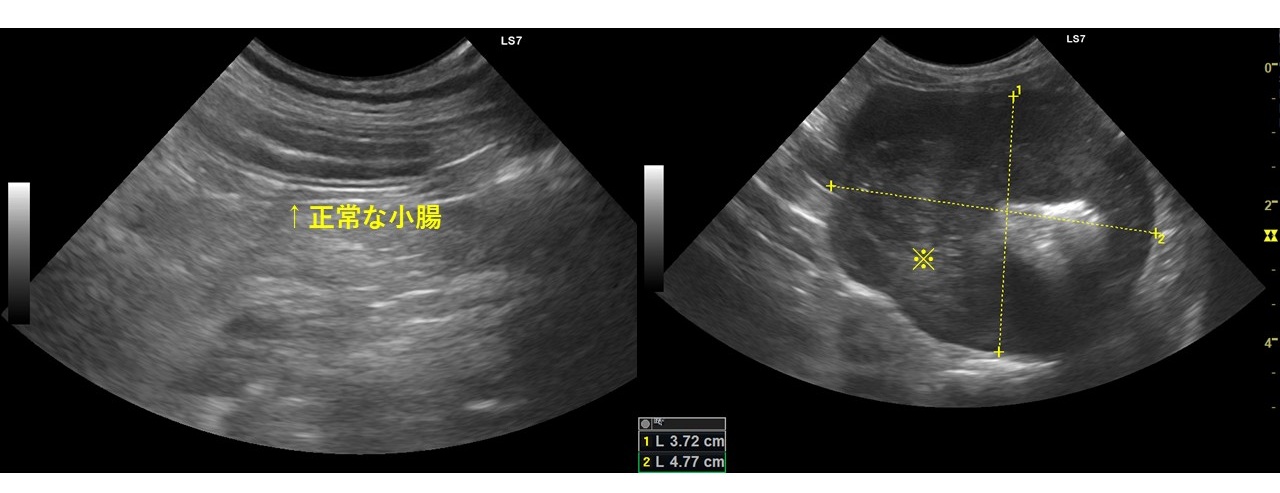

消化管型リンパ腫の症例。お腹の中にしこりがあり検査実施。左が正常な小腸であり、小腸壁が層構造に見えている。右が消化管型リンパ腫で小腸が腫瘤状になっている。